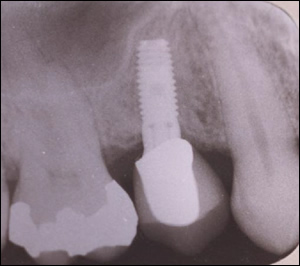

Fig 3: Using the Summers Technique, the floor of the maxillary sinus was repositioned "non-surgically". A bone graft and a dental implant were easily placed.

Fig 4: Notice the repositioned sinus floor.